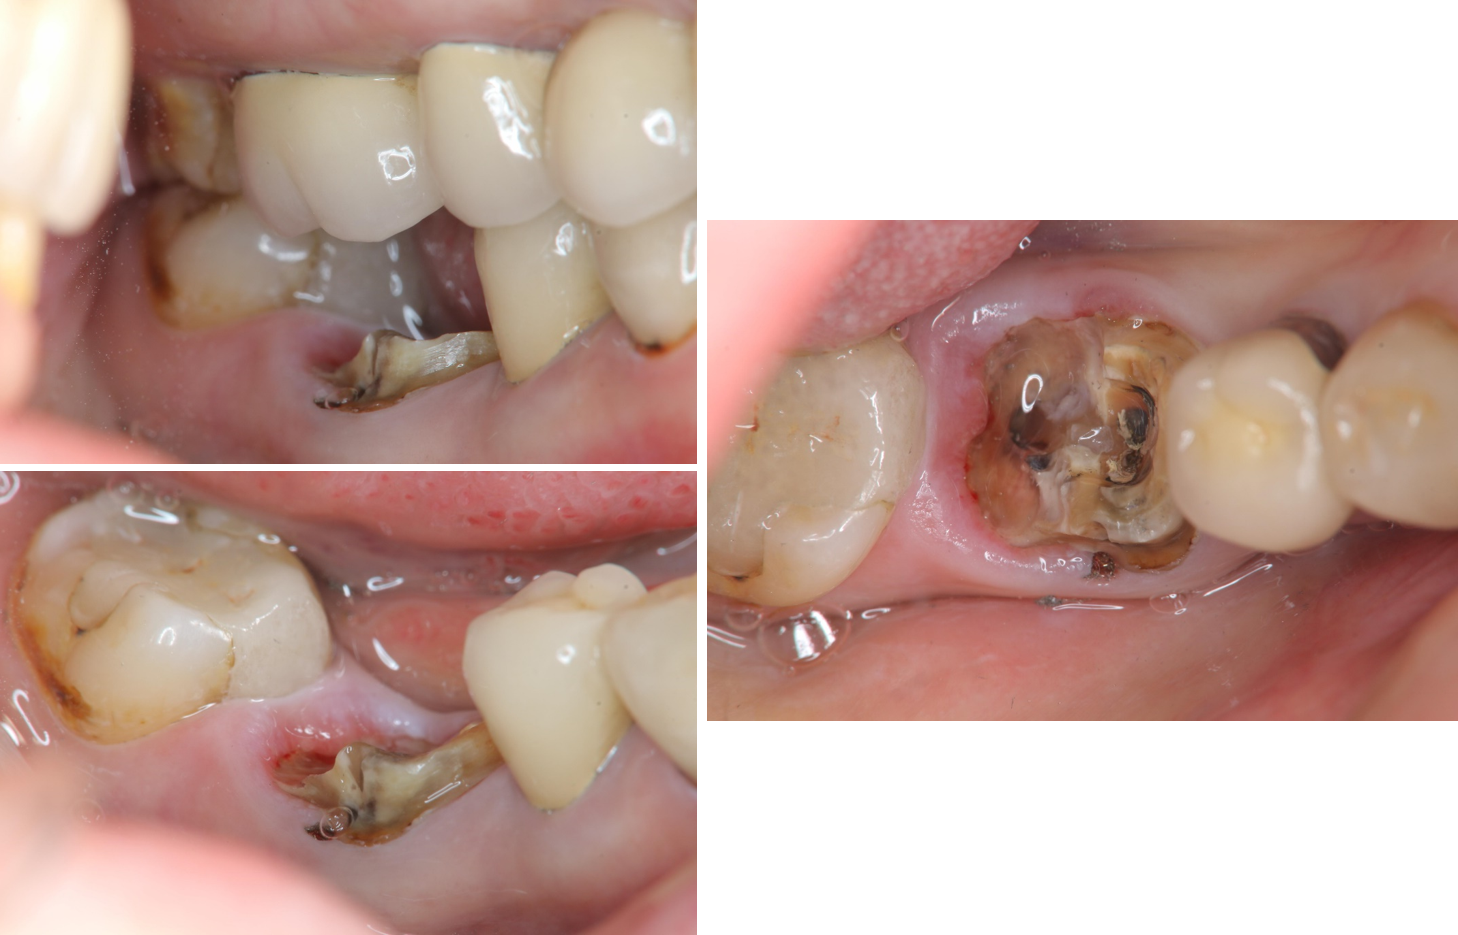

治療前,左下第一大臼齒嚴重蛀牙

治療前,蛀牙至牙根處